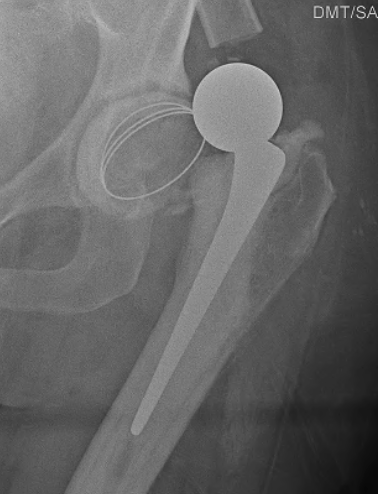

Dislocated constrained liner

Successful reduction constrained liner

Unsuccessful reduction constrained liner